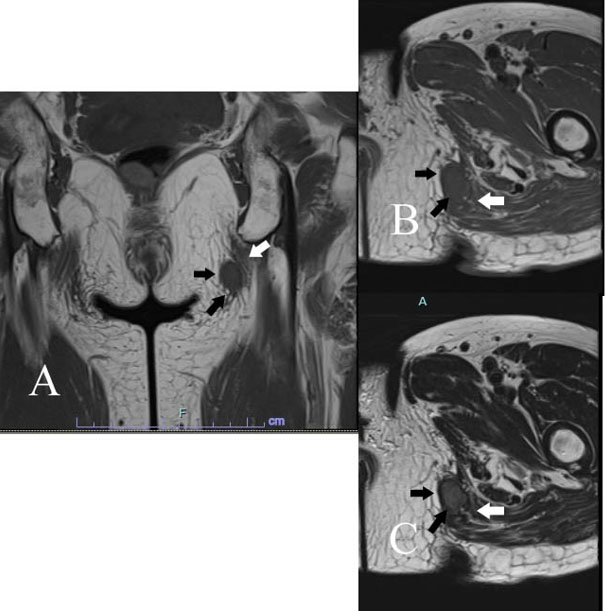

A 65-year-old woman had six-month of left buttock painless soft tissue mass. She underwent polypectomy for colon adenoma one year ago. On physical examination, a rubbery and movable mass in the buttock was palpable, which measured a size of 17 mm × 17 mm using vernier caliper. Coronal and axial MRI showed a mass in the subcutis of buttock and attached to the gluteal fascia that had homogeneous intermediate intensity on T1-weighted image (Figure 4A and Figure 4B). Corresponding axial T2-weighted image revealed a mass to be inhomogeneously high signal intensity (Figure 4C).

Figure 4: Case 3. Angiofibroma of soft tissue in the buttock coronal (A) and axial (B) MRI shows a mass in the subcutis of buttock (black arrows) and attached to the gluteal fascia (white arrow) that had homogeneous intermediate intensity on T1-weighted image (TR/TE=476/9.90). Corresponding axial T2-weighted image (TR/TE=3110/105) reveals a mass to be inhomogeneously high signal intensity (C).